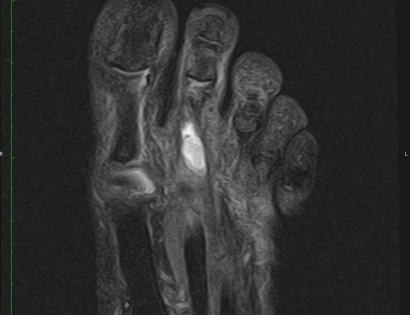

• • The work-up often consists of a physical examination, X-rays, CT scans, MRI, and sometimes bone scans are required. CT scans can be used to check for subtle mineralization that may help with the diagnosis.

Radiographic imaging is used to help form a diagnosis. These include X-Ray, MRI, CT and Bone Scans

An example of an MRI is shown.